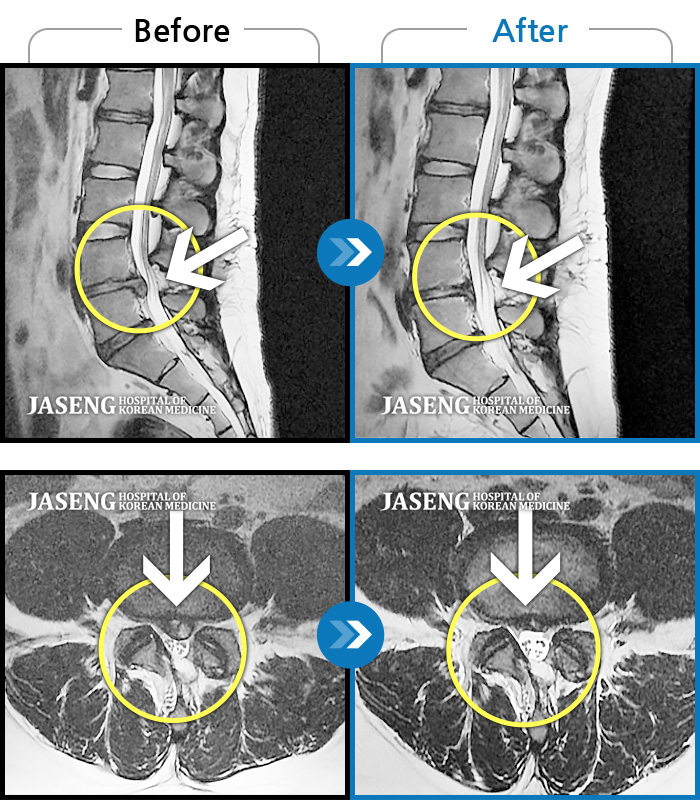

MRI 치료사례

허리 디스크 수술 후 재발된 디스크 환자